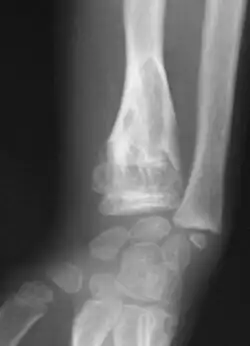

-

X-ray showing calcified enchondromas localized in finger a 37-year-old patient affected with Ollier disease -

X-ray showing enchondromas localized in the humerus of a 37-year-old patient affected with Ollier disease -

X-ray showing enchondromas localized in the lower part of the radius of a 37-year-old patient affected with Ollier disease -

Abnormal bone growth such as shortening or thickening and deformity may be observed in patients of Ollier disease. These bone lesions are visible at birth using radiography but are usually not screened or examined for until clinical manifestations present during early childhood. However, some patients may exhibit no signs of any symptoms.[1] One study found thirteen to be the mean age of diagnosis in patients with Ollier disease. In an X-ray, there would normally be the presence of several homogeneous lesions of an oval or elongated shape with bone edges that are slightly thickened.[3] With age, these lesions may calcify and appear as diffusely minute spots or stippled. Fan-like septations or streaks would be indicative of the presence of several enchondromas. Early detection and consistent and repeated monitoring is important in order to prevent and treat any potential bone neoplasms.